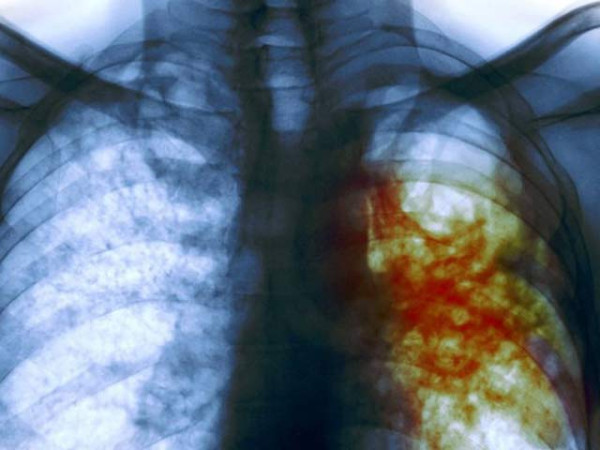

وٹامن سی کو اگر دواؤں کے ساتھ ملاکر دیا جائے تو اس سے ٹی بی کا مؤثر انداز میں خاتمہ ممکن ہے۔ فوٹو: فائل